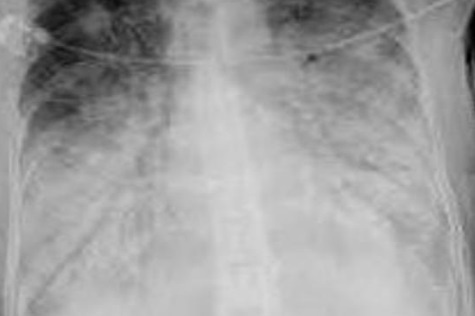

¿Cuál es el dx?

Carcinoma broncogénico